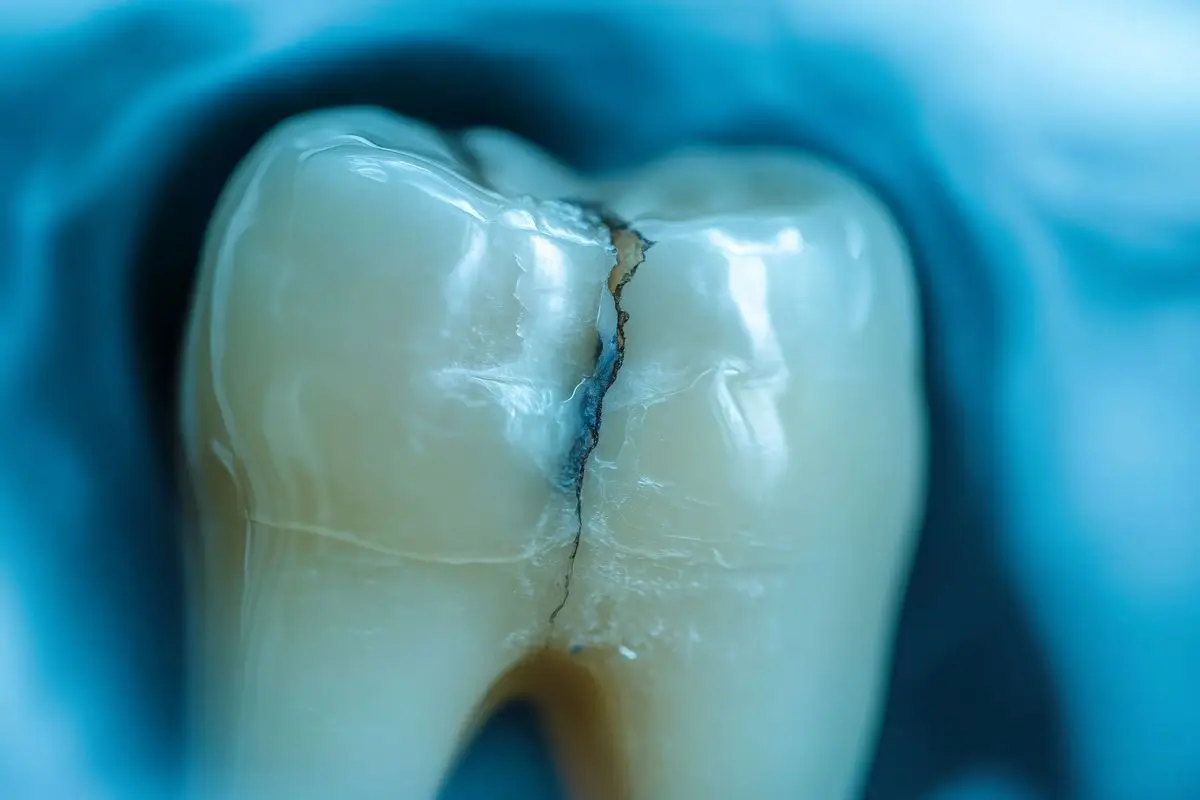

A cracked tooth is a tooth that has become damaged by a break or fracture. Cracks can vary in size and severity — some may be harmless, while others can affect the inner tissues of the tooth and require treatment.

• Cracked Tooth – A crack that runs from the biting surface of the tooth towards the root. It may extend below the gum line but usually keeps the tooth in one piece. The inner pulp is often affected.

• Split Tooth – A severe crack that splits the tooth into two parts, often the result of an untreated crack.